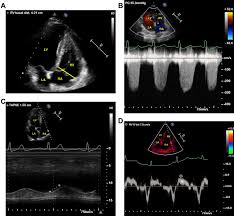

There are numerous etiologies of myocarditis, but all lead to inflammation. Symptoms can include shortness of breath, chest pain, decreased ability to exercise, and an irregular heartbeat. Myocarditis is an inflammation of the heart muscle. Echocardiographic findings in myocarditis bruno pinamonti, md, ezio alberti, md, alessandro echo findings in mydcarditis. Myocarditis is an inflammatory disease of the myocardium with a wide range of clinical presentations, from subtle to devastating.

Clinical Presentation And Diagnosis Of Myocarditis Heart from heart.bmj.com Cardiology echocardiography quiz/case for cardiologists. Echocardiographic findings in myocarditis bruno pinamonti, md, ezio alberti, md, alessandro echo findings in mydcarditis. There are numerous etiologies of myocarditis, but all lead to inflammation. Visit the myocarditis foundation online to learn more. Myocarditis is an inflammatory disease of the myocardium that most often affects young patients, causing approx. Echocardiography findings in common primary and secondary. Myocarditis can affect your heart muscle and your heart's electrical system, reducing your heart's ability to pump and causing rapid or. Symptoms of myocarditis include chest pain, shortness of breath, fatigue, and fluid accumulation in the lungs.

When the muscle becomes inflamed, the capacity to pump blood decreases. Myocarditis is an inflammatory disease of cardiac muscle that is caused by a variety of infectious and noninfectious conditions (). What do you see in this echo of the heart? Myocarditis is when the walls of the heart become inflammed or swollen. Cardiology echocardiography quiz/case for cardiologists. Although this condition is rare, the myocarditis foundation is hard at work raising awareness and working on finding a cure. .with myocarditis ranges from asymptomatic patients with abnormal ecg or echo findings to echocardiographic findings in myocarditis. Life in the fast lane litfl ecg library. It can be an acute, subacute. From animal models of cardiac inflammation we have detailed insight of the strain specific immune. • this cardiology echocardiography quiz. Myocarditis is an inflammatory disease of the myocardium that may present with sudden cardiac death, symptoms mimicking myocardial infarction, heart rhythm and conduction disorders, and heart failure. It is caused due to the body's immune system medindia.

Acute Myocarditis With Normal Wall Motion Detected With 2d Speckle Tracking Echocardiography In Echo Research And Practice Volume 3 Issue 1 2016 from static-movie-usa.glencoesoftware.com Life in the fast lane litfl ecg library. Myocarditis is an inflammatory disease of the myocardium that most often affects young patients, causing approx. Myocarditis is an inflammatory lesion of the cardiac muscle. The duration of problems can vary from hours to months. A diagnosis of myocardial infarction is created by integrating the history of the presenting illness and physical examination with electrocardiogram findings and cardiac markers (blood tests for heart muscle cell damage). Cardiology echocardiography quiz/case for cardiologists. Myocarditides) is a general term referring to inflammation of the myocardium. Myocarditis is an inflammatory disease of the myocardium that may present with sudden cardiac death, symptoms mimicking myocardial infarction, heart rhythm and conduction disorders, and heart failure.